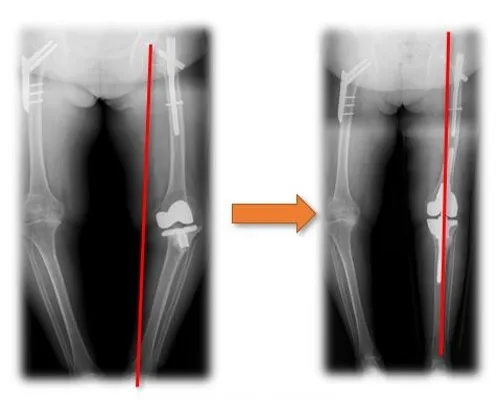

Total hip replacement for osteoarthritis secondary to hip dysplasia